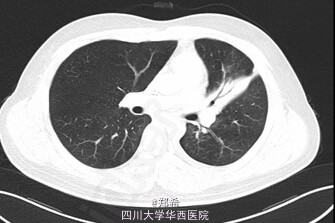

患者21岁,因“咳嗽、咳痰1+年”入院。患者于1+年前无明显诱因出现咳嗽、咳痰,咳黄色脓痰,量少,伴潮热盗汗,于当地医院住院治疗,活检示:支气管内膜结核(具体报告未见),遂予一线抗结核药物治疗,半年后于我院呼吸内科住院调整为二线抗结核药。6+月前因“支气管结核狭窄”于外院安置左主支气管支架,后多次于复查纤支镜取支气管支架均未取出,并于我院查TB-DNA阴性。于1-月前查胸部增强CT示:左肺上叶舌段实变肺不张,作肺内散在斑片条索影,左主支气管内见高密度支架影,支架内可见少许软组织密度影,其远端左主支气管管壁稍厚,多系炎症;左肺门淋巴结增大;心包少量积液;左侧胸膜增厚,左侧胸腔少量积液。查体:左肺呼吸音低。初步诊断:1、左主支气管狭窄2、左主支气管支架置入术后3、支气管内膜结核4、糖尿病。处理:全麻下行左主支气管支架取出+左全肺切除术。手术顺利,术后入ICU继续治疗。讨论:肺结核最严重的并发症之一就是能够引起支气管狭窄,支气管胸膜瘘,因此,要按照结核治疗标准早期、规律、全程、联合用药,此病例属于典型结核引起支气管狭窄,最后不得不切除全肺。